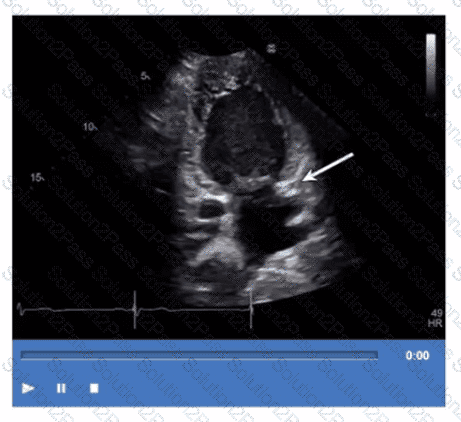

Which structure is the arrow pointing to in this video?